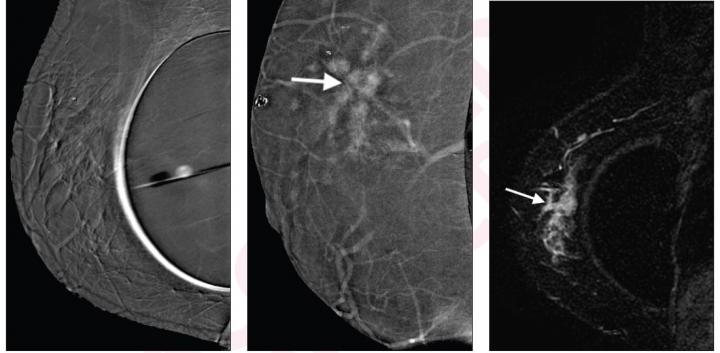

image: Left to right: Subtraction right mediolateral oblique (MLO) CEM was non-diagnostic because of artifact, potentially due to motion misregistration from extended exposure time; subtraction right MLO implant displaced CEM image shows 5.8 cm enhancing mass (arrow); contrast-enhanced MRI sagittal subtraction image shows concordant mass (arrow).

Noting that CEM has not been investigated in women with breast augmentation, Molly Carnahan and her Mayo Clinic team in Phoenix, AZ, concluded, "the findings suggest a possible role of CEM for staging in women with breast augmentation and contraindication or limited access to MRI."

The index cancer histology was invasive ductal carcinoma (IDC) in 15 (88%) women, invasive lobular carcinoma (ILC) in 1 (6%), and ductal carcinoma in situ in 1 (6%). Median index cancer size was 2 cm, and 2 (12%) index cancers were mammographically occult. Ultimately, CEM and MRI were concordant for the index cancer in all 17 women.

Six additional lesions were demonstrated by CEM and confirmed by MRI in 6 (35%) women: 3 multifocal, 1 multicentric, 2 contralateral. Two of these lesions revealed malignant histopathology: 1 IDC, 1 ILC.

"MRI did not identify any additional cancers not identified on CEM," the authors of this AJR article added.